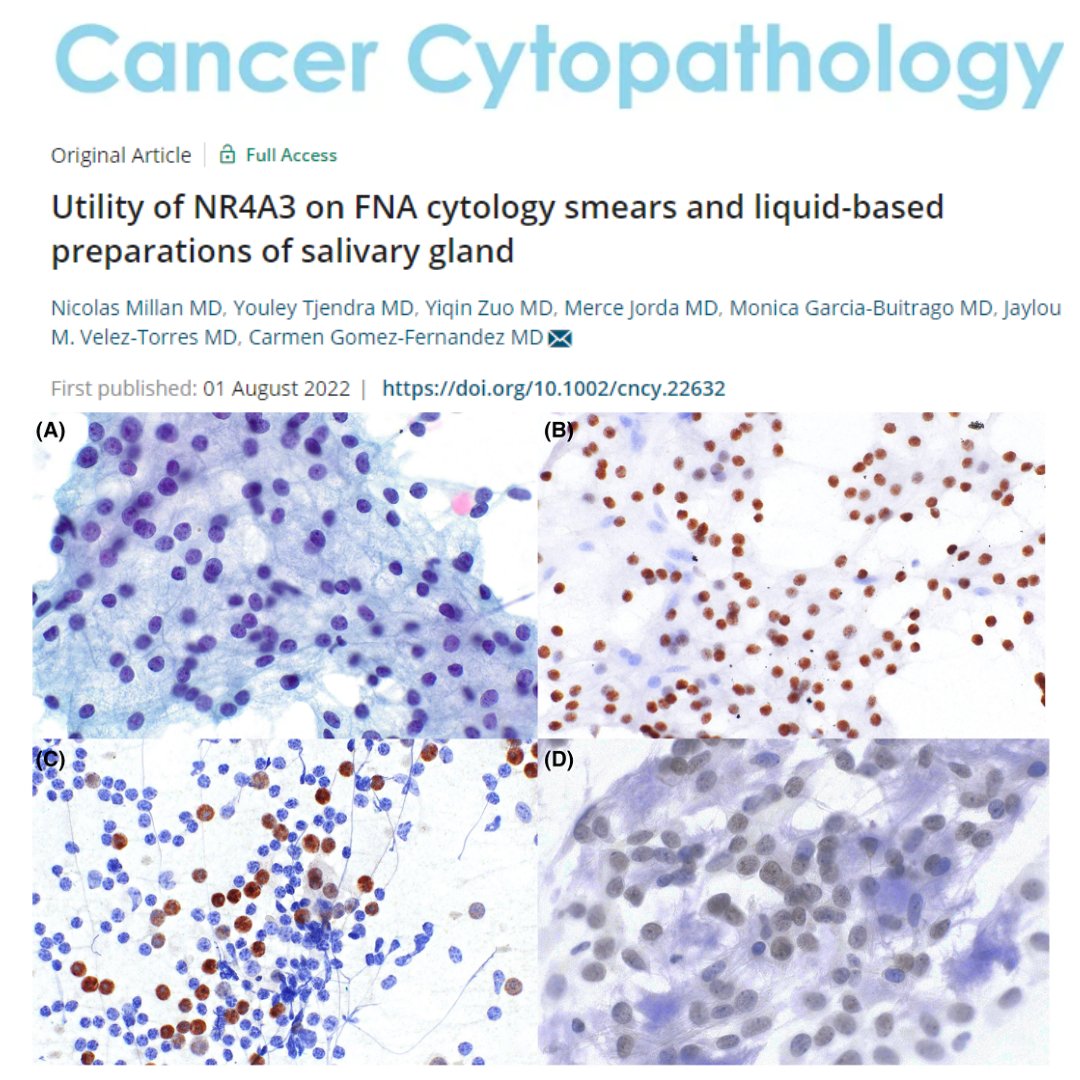

NR4A3 immunocytochemistry can be used directly on FNAC conventional smears & liquid-based cytology to reliably distinguish acinic cell carcinoma from its mimickers. This may be useful in cases where a cell block preparation is unavailable or inadequate. acsjournals.onlinelibrary.wiley.com/doi/full/10.10…